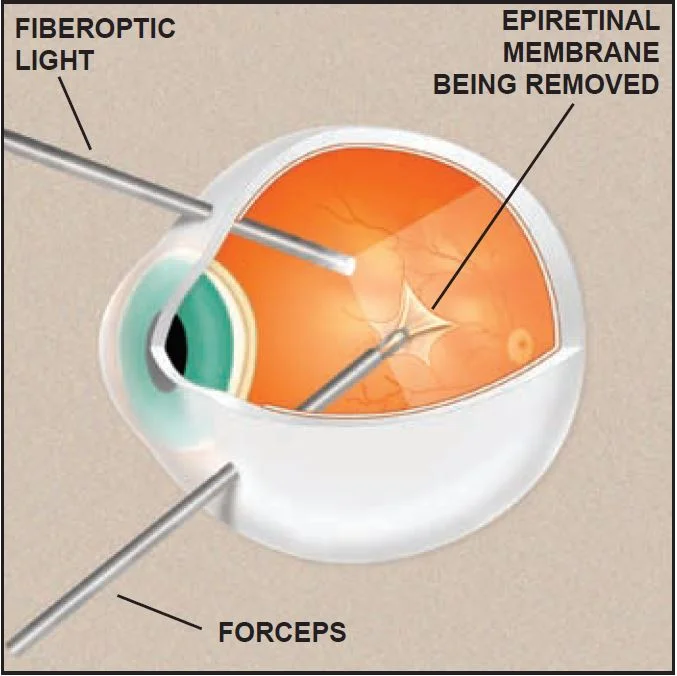

Epiretinal membrane – Mayo Clinic

Epiretinal membrane definition, causes, symptoms, diagnosis & treatment

Epiretinal Membranes Diagnosis and Treatment – Kam Balaggan

Epiretinal membrane – Edgbaston Eye Clinic